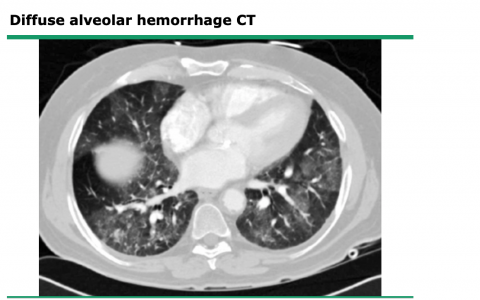

弥漫性肺泡出血的常见病因

弥漫性肺泡出血(diffuse alveolar hemorrhage, DAH)综合征的特点是血液进入肺泡腔,原因是肺泡-毛细血管基底膜破裂。基底膜破裂的原因是小动脉、小静脉或肺…